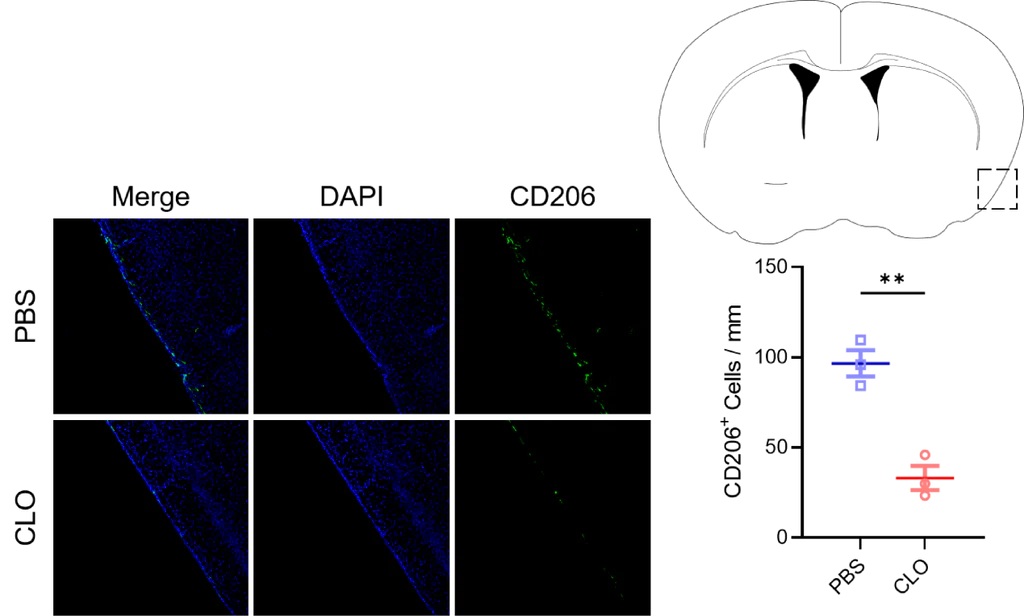

1. Case Study: Efficient Depletion of Perivascular Macrophages in the Mouse Brain

Figure 1. Efficient depletion of perivascular macrophages in the brain following intracisternal administration of Yeasen Macrophage Depletion Reagent (Cat. No. 40337ES).

Mice received a single injection of 4 µL clodronate liposomes (CLO) into the cisterna magna; control animals received an equal volume of PBS. Brain tissues were collected 7 days post-injection and sectioned for immunofluorescence staining using anti-CD163 antibody (Cell Signaling Technology, #24595) to label perivascular macrophages. Quantification of macrophages per unit vessel length showed a significant reduction in the CLO group (33.10 ± X.XX) compared to PBS controls (96.59 ± X.XX), corresponding to a ~66% decrease (or approximately 34% of control levels). Note: If CD26 was intended instead of CD163, please confirm—CD163 is a canonical marker for perivascular macrophages in the CNS; CD26 is atypical for this population.